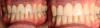

Figure 12 shows the temporary abutment (left panel) after the implant and connective tissue graft were placed, and the patient 2 weeks postoperatively (right panel). Seven years later, the restoration remains sound (Figure 13).

Fig 12. Left panel: temporary abutment in the patient with the congenitally missing tooth No. 10. Right panel: Two weeks postoperatively after the implant and connective tissue graft placement. (Images courtesy of Dr. Keith Progebin.)

Figure 12

Fig 13. Patient with congenitally missing tooth No. 10 at 7 years postoperatively.

Figure 13